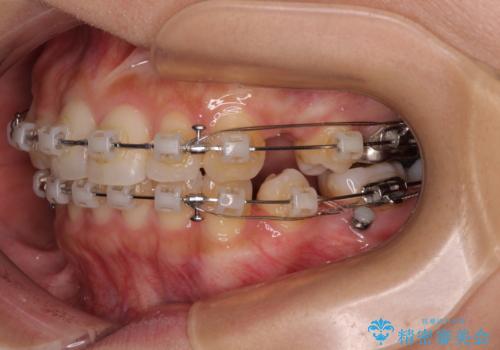

- 矯正装置

- クリアブラケット

上下左右の第一小臼歯4本を抜歯して治療を行うことがセオリーでしたが、左下は第二小臼歯が銀歯であったため、イレギュラーではありますが、そちらを抜歯しました。

その影響で治療期間は長くなりましたが、処置していない歯を保存することができました。